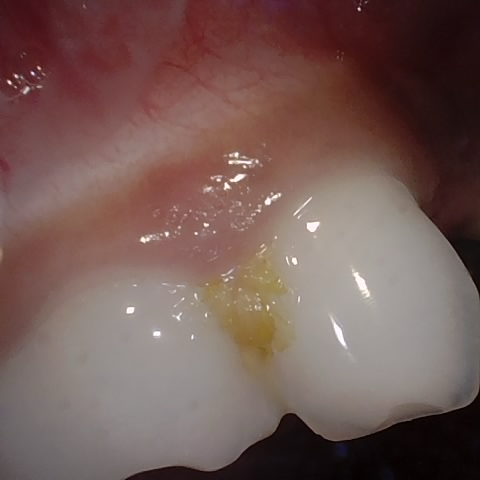

NHD27230

Annotated as "Good"

Original Image Rendering Image